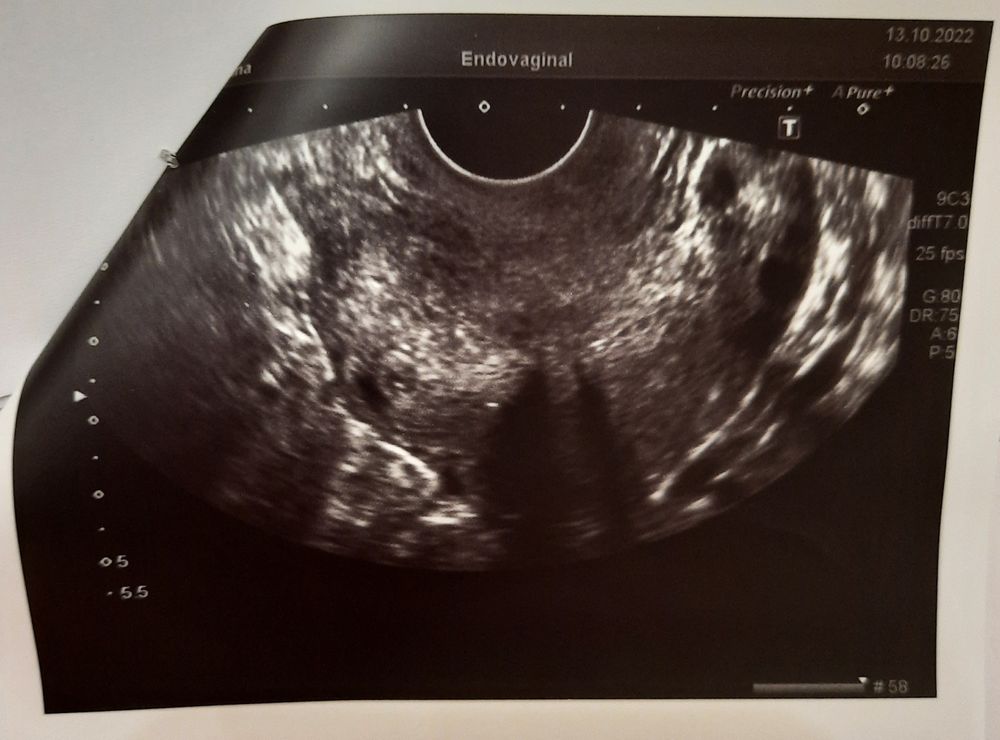

Синдром Ашермана?

Здравствуйте! Пожалуйста проконсультируйте, проблема в следующем: после вторых родов в январе 2022г. в полости матки остались остатки плацентной ткани с которыми меня благополучно выписали на 7 сутки из родильного дома. На 10 сутки была экстренно госпитализирована, перенесла 2 выскабливания. После вышеперечисленного ещё 1 месяц долечивалась амбулаторно так как в полости матки ещё оставались сгустки крови. В мае 2022 начались первые месячные после родов, они были очень скудные, можно сказать просто мазали 3 дня и на этом всё. В октябре обратилась с данным вопросом к врачу, была направлена на УЗИ ( проведено на современном дорогостоящем аппарате 3Д), после чего мне поставили диагноз Синдром Ашермана под вопросом? Также мне посоветовали прийти на консультацию через год, а пока ничего не предпринимать, сказали можно не предохраняться так как забеременеть я всё равно теперь не смогу. Скажите действительно ли на снимке УЗИ видно спайки? Возможно ли от них вылечиться, восстановить менструацию и смогу ли я забеременнеть после этого?